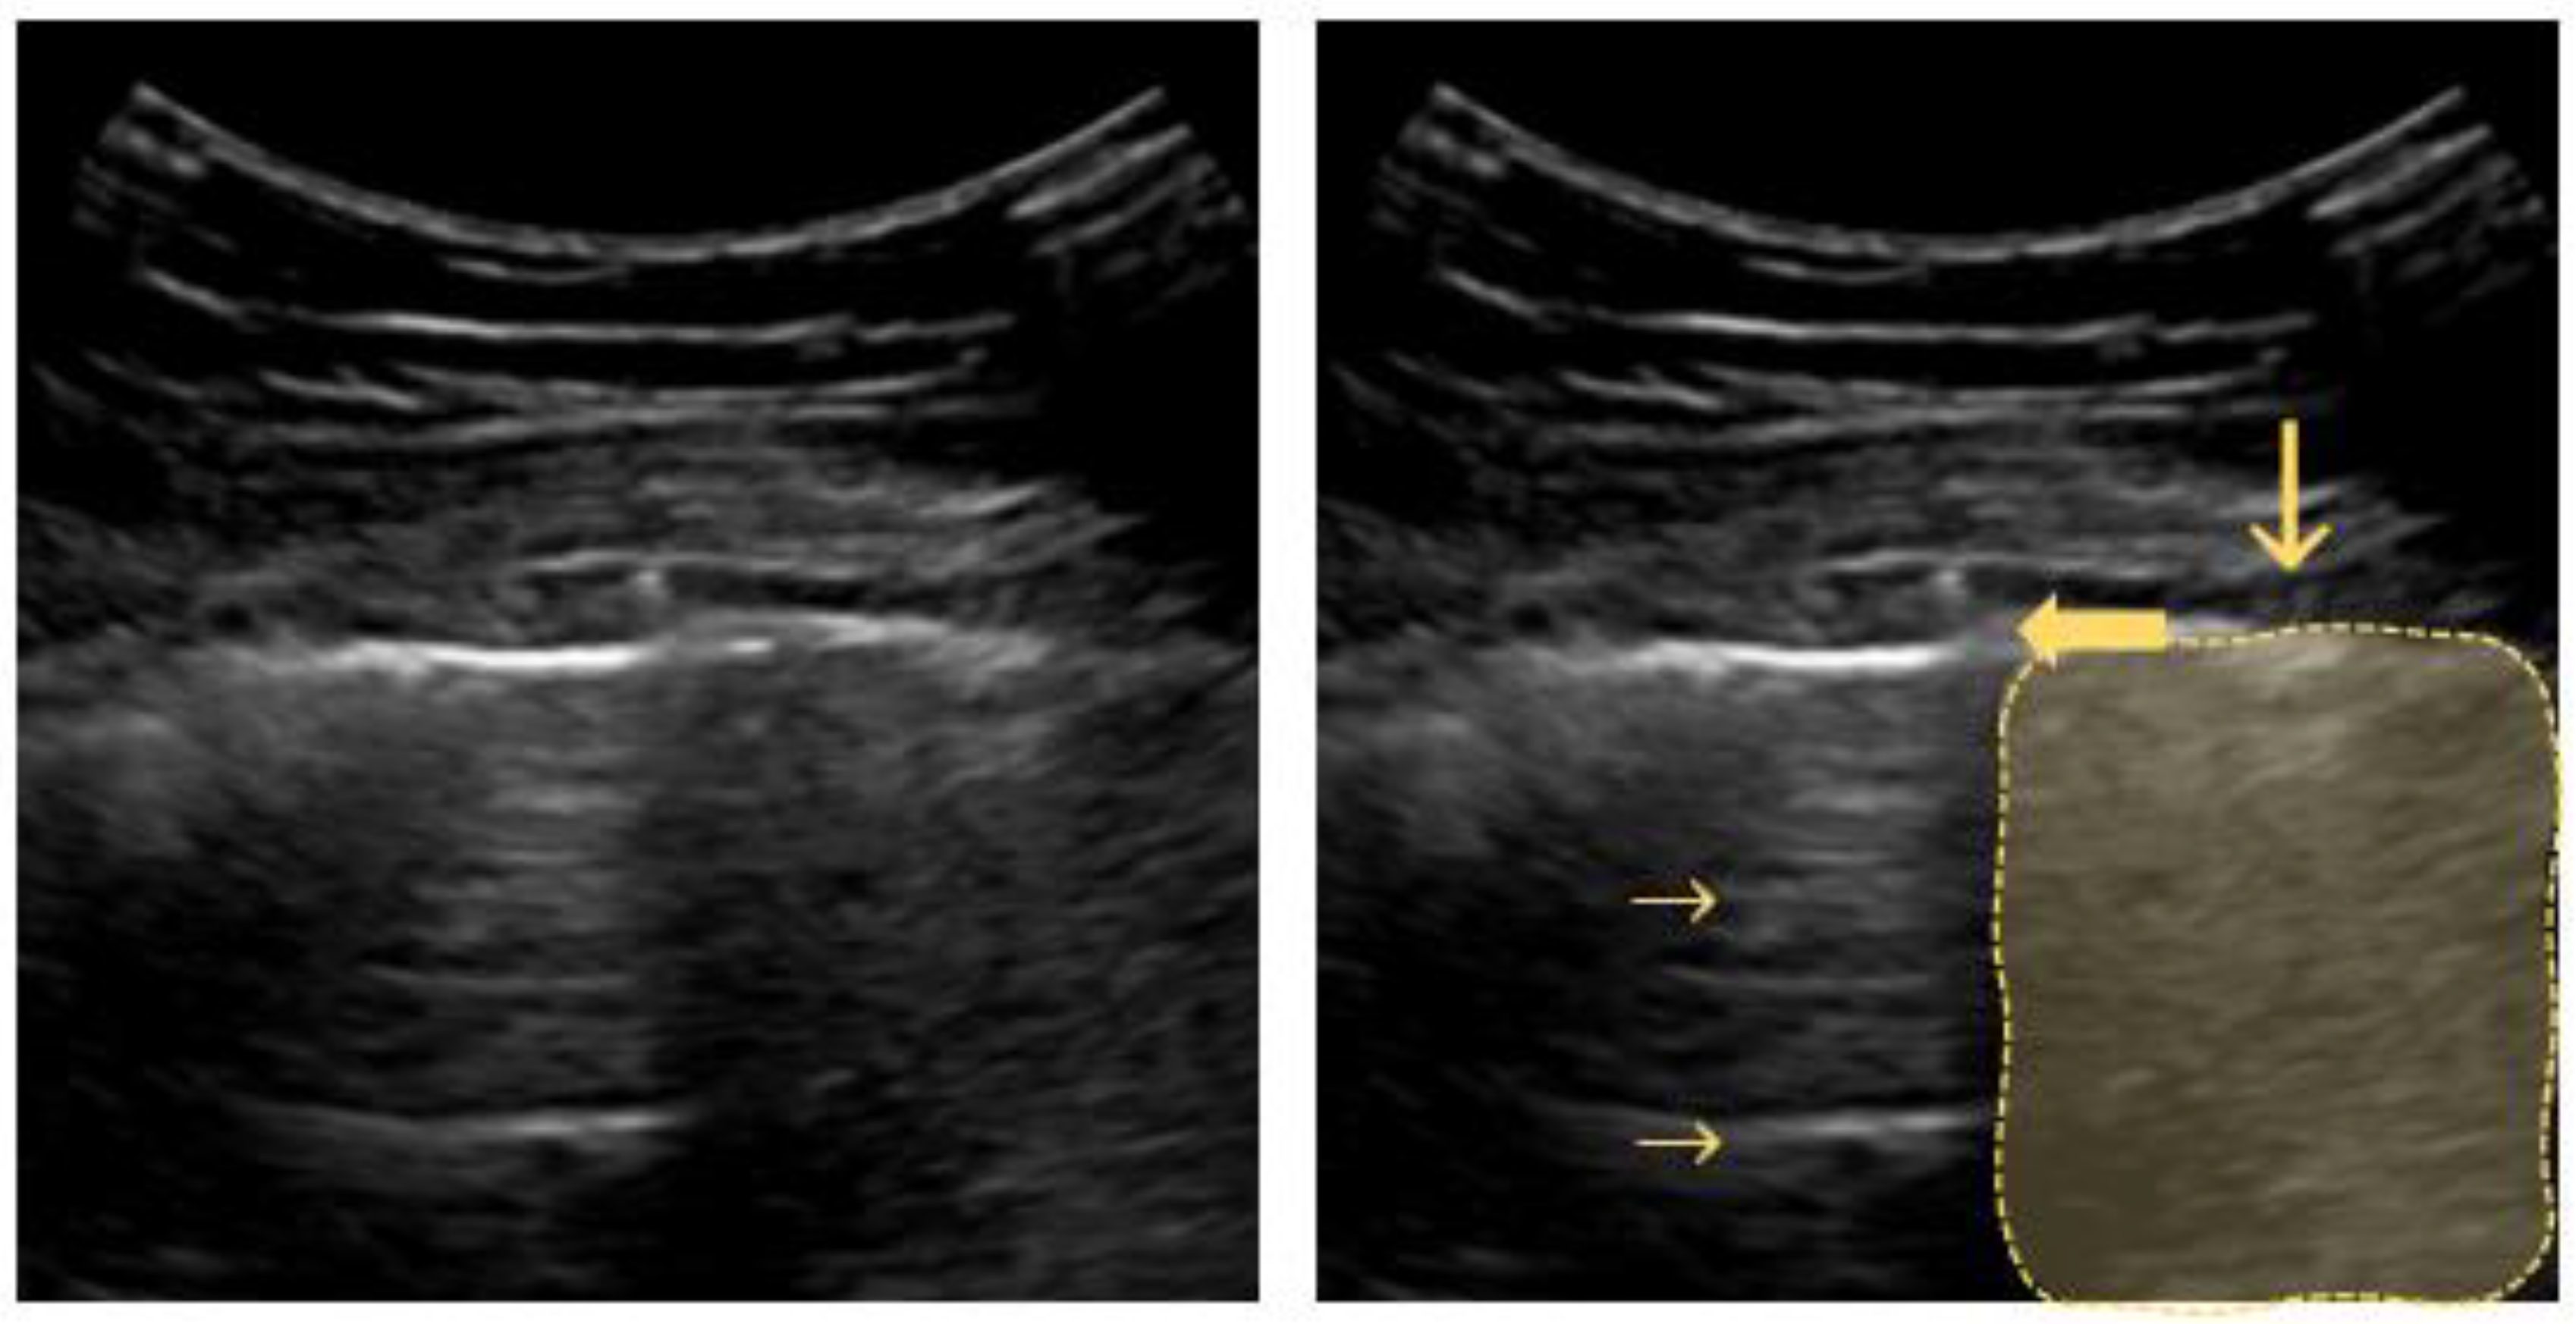

4.2. Interstitial Syndrome